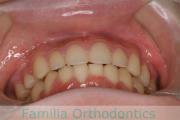

No.21V-614

- 過蓋咬合

- 叢生

- 15歳

- 女性

- 上:

- 44

- 下:

- 8558

- FEA

- 90万円

左下の奥歯が内側に倒れているのを治したいということで来院されました。かみ合わせが深い、上顎前突(出っ歯)の患者さんでした。上下左右から小臼歯を抜歯して、大臼歯を起こしながら治療を行いました。約3年、35回程度の通院をしていただきました。

かみ合わせが深いため、治療を行わないと前歯の裏側の歯茎を咬んでしまうリスクがありました。